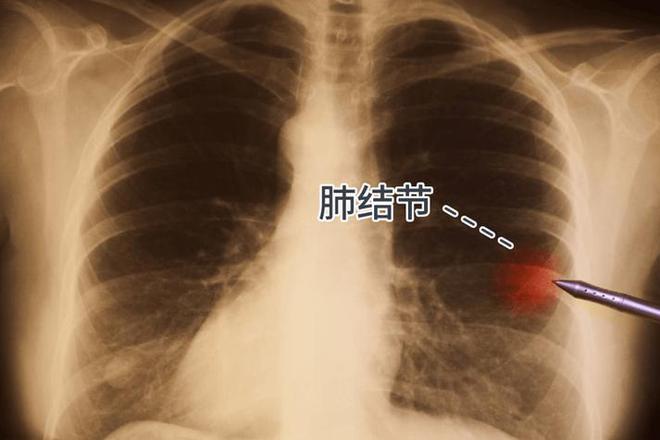

在这个世界上,有一种疾病,它悄无声息地侵蚀着我们的肺,那就是空洞型肺结核。它像一个隐形的敌人,潜伏在我们的身体里,慢慢地,无情地破坏着我们的健康。每当夜深人静的时候,我总会感到一种难以言说的孤独和恐惧,不知道这个可怕的空洞何时才能闭合。

许多患者和我一样,都在无助地等待着那个奇迹般的时刻——空洞闭合。但是,这个过程并不简单,它需要时间,需要耐心,更需要坚强的意志。有人说,空洞型肺结核的闭合可能需要几周,也可能需要几年。这种不确定性像一块沉重的石头压在心头,让人喘不过气来。

在这漫长的等待中,我学会了坚强,学会了与病魔抗争。我知道,每一个不放弃的日子,都是向健康迈进的一步。虽然未来的路还很长,但我相信,只要我们坚持下去,总有一天,那个空洞会闭合,我们会重获新生。